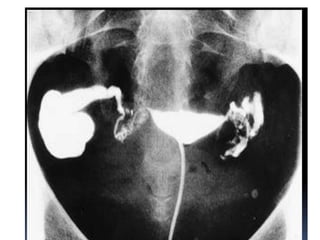

• Hydrosalpinx

• Common cause- salpingitis

• Distal tubal occlusion- dilatation of proximal

segment

• Hydrosalpinx • Commoncause- salpingitis • Distal tubal occlusion- dilatation of proximal segment